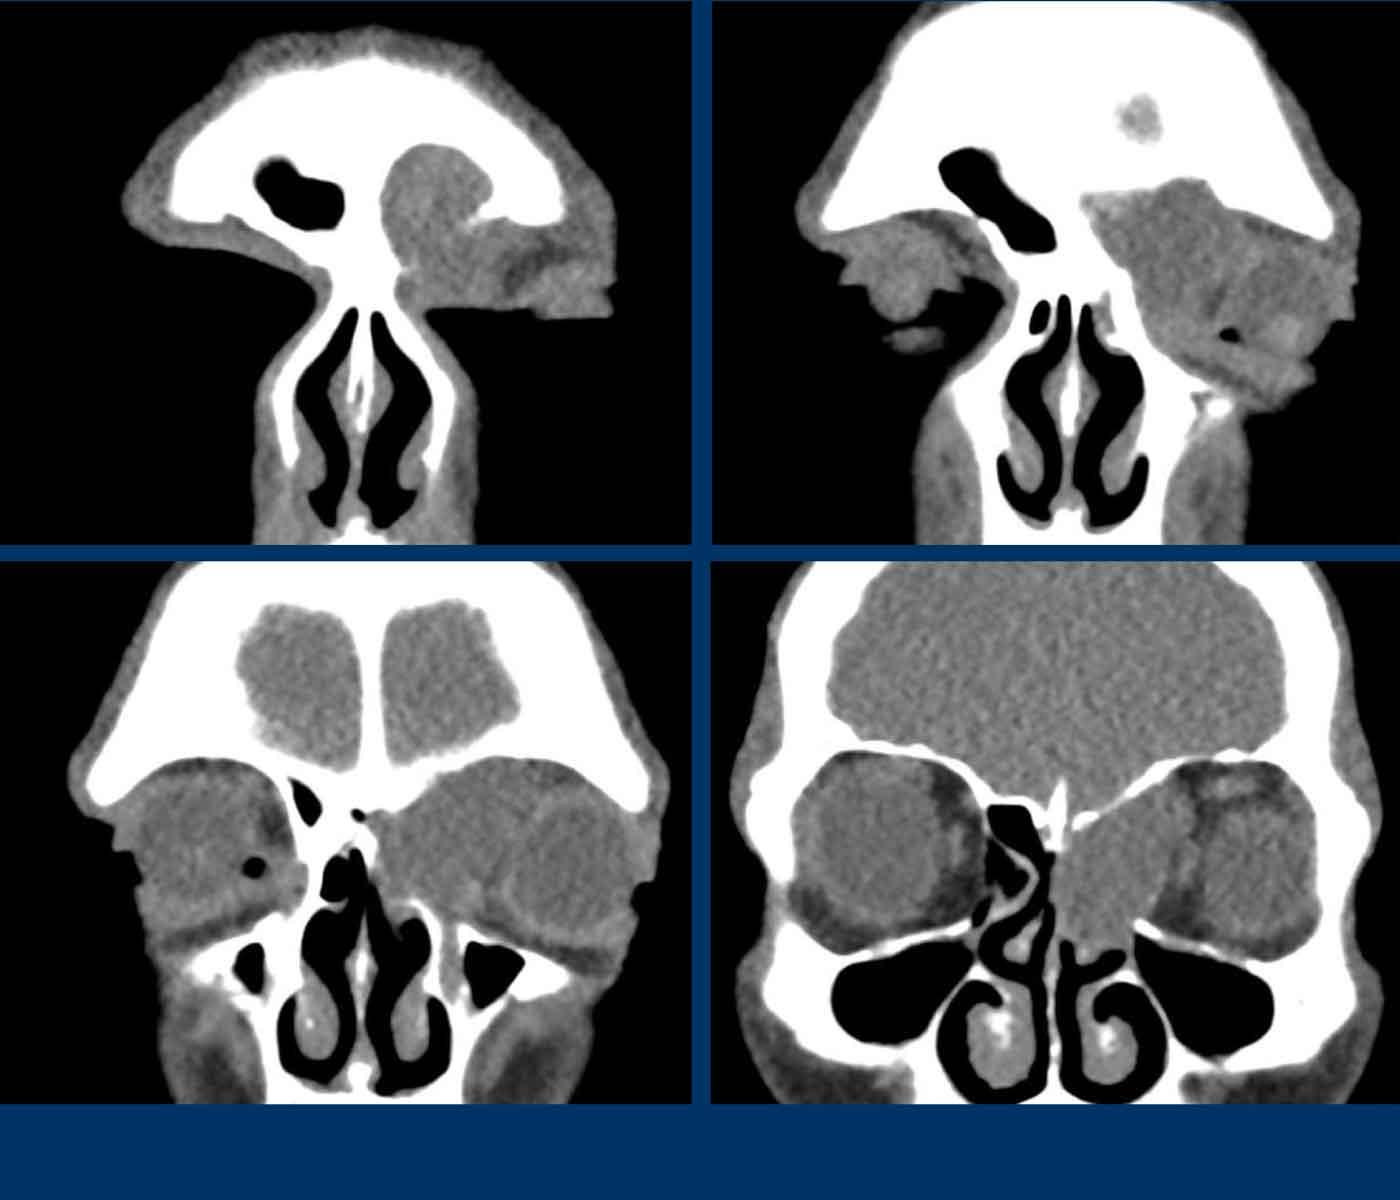

Các hình ảnh này của bệnh nhân nam 47 tuổi, có triệu chứng căng tức vùng trán.

- Tổn thương giãn rộng đẩy nhãn cầu trái sang bên.

- Tổn thương có bờ rõ nét.

- Tổn thương xuất phát từ xoang trán trái.

- Thành trong hốc mắt trái (đầu mũi tên đen) và nền sọ (đầu mũi tên trắng) bị mỏng đi, nhưng không có phá hủy xương.

MRI được thực hiện để xác nhận chẩn đoán nhiều khả năng nhất là nang nhầy…

MRI cho thấy tổn thương giãn rộng chỉ có ngấm thuốc tương phản từ ở vùng viền ngoại vi.

Không có ngấm thuốc bên trong tổn thương.

Điều này xác nhận chẩn đoán nang nhầy.